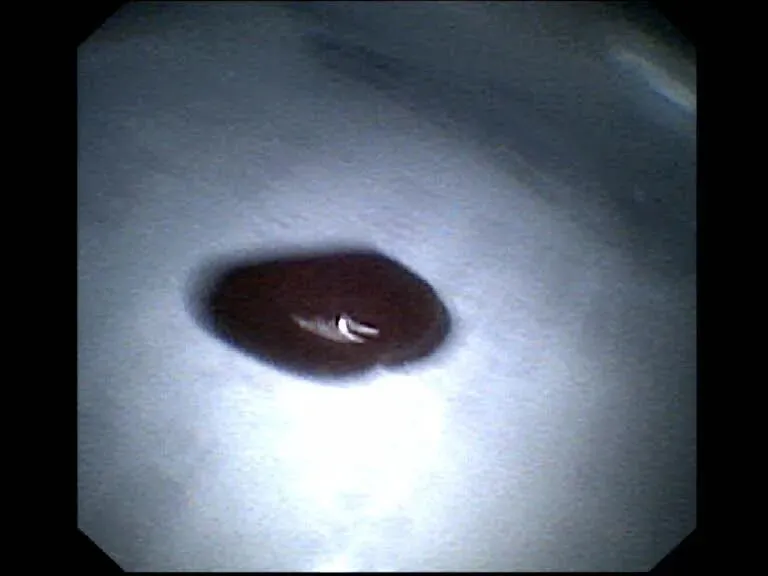

经管医师瞅准时机,稳步操作,在患者吸气瞬间,迅速出钳,精准、稳定地夹住蚂蟥体部,随后小心翼翼地调整角度,最终将这只“潜伏”已久的害虫完整取出。术后观察,蚂蟥长约6.5厘米,取出后患者气道内活动性出血立即停止,且咳嗽症状迅速缓解。